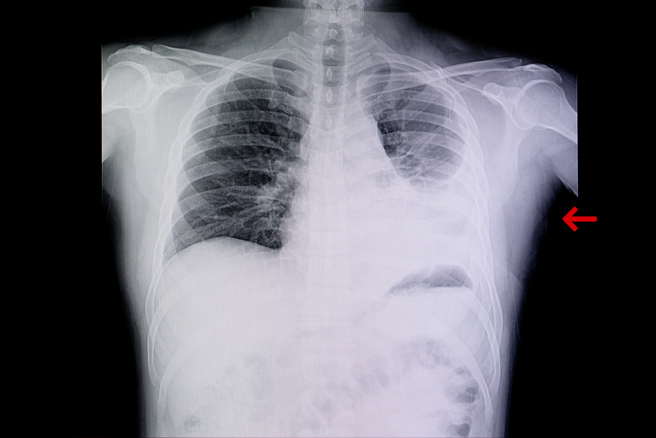

大陸疫情升溫,近日傳出有許多人出現「白肺」症狀,恐怖的名稱讓不少民眾聽了很害怕,胸腔重症科醫師蘇一峰表示,所謂的白肺,正確名稱應該是肺炎重症或急性呼吸窘迫症,全世界的加護病房裡面都會有,他自己手頭上也有幾個白肺患者,因此這並不是大陸才有的疾病。

蘇一峰昨在臉書上分享,傳大陸因為疫情出現了「白肺」,讓許多人聽了很恐慌,但其實所謂的白肺,正確名稱應該是「肺炎重症」或「急性呼吸窘迫症」。而這個狀況全世界的每家醫院裡面都會有,並不是只有大陸才有。

蘇一峰表示,他自己手頭上目前也有「白肺」患者,應該說,每家醫院的加護病房裡面應該都會有一大堆白肺的患者喔!而他應該也可以算是台灣的白肺專家了。